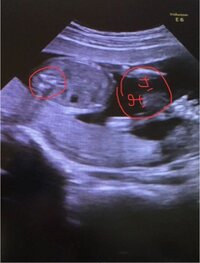

妊娠17週目のエコー写真です 丸で囲んでいる白い点3つは何なのか Yahoo 知恵袋

妊娠についてです エコー写真をもらいました これは双子でしょうか Yahoo 知恵袋